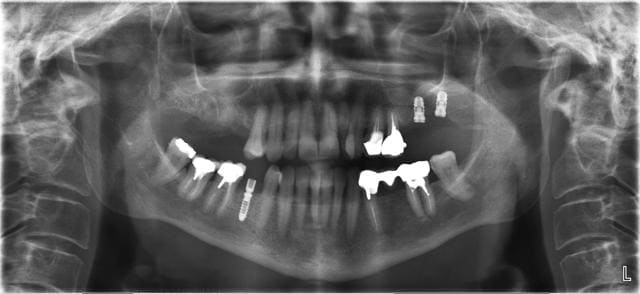

La suite des extractions et comblement par matri bone Prf.

Résultat rx et visuel à 8 jours.

Pour le moment rien que du très classique.